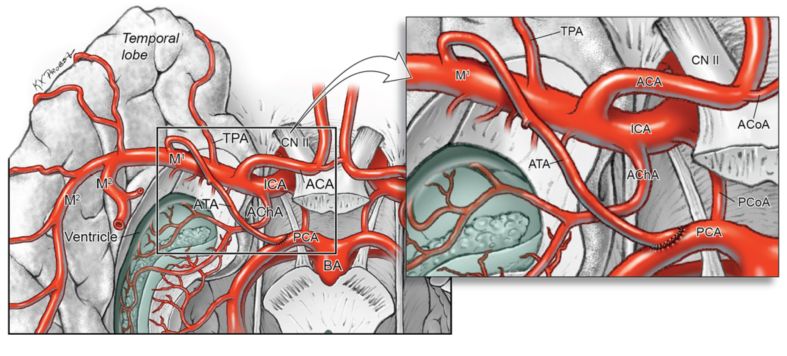

15.颞前动脉对后循环上部血管重建的解剖学研究

Revascularization of the upper posterior circulation with the anterior temporal artery: an anatomical feasibility study.

PMID: 28937325 DOI: 10.3171/2017.3.JNS162865

包括不可夹闭动脉瘤在内的许多疾病,可能需要对后循环上部(upper posterior circulation , UPC)血管(包括小脑上动脉[superior cerebellar artery, SCA]和大脑后动脉[posterior cerebral artery, PCA])进行搭桥。研究通过对14具尸头行颞前动脉(anterior temporal artery, ATA)-SCA和ATA-PCA搭桥,评估ATA对后循环上部血管重建的解剖可行性。

结果显示,有17支ATAs被解剖游离,成功吻合14支。PCA吻合处和SCA吻合处距其基底动脉起始部的平均距离分别为14.2 mm和10.1 mm。但有3支ATAs血管因与颞中动脉有共同的岛盖部起始点,故长度达不到后循环上部。通过以上研究,ATA是颈内动脉上对后循环上部行血管重建的理想供血血管。行眶颧入路暴露ATA,无需移植血管,避开复杂困难的多重血管吻合,可直接高效的进行端侧吻合。

【祝海平】